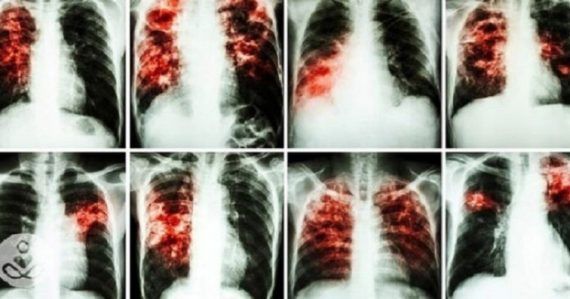

• Καρκίνος